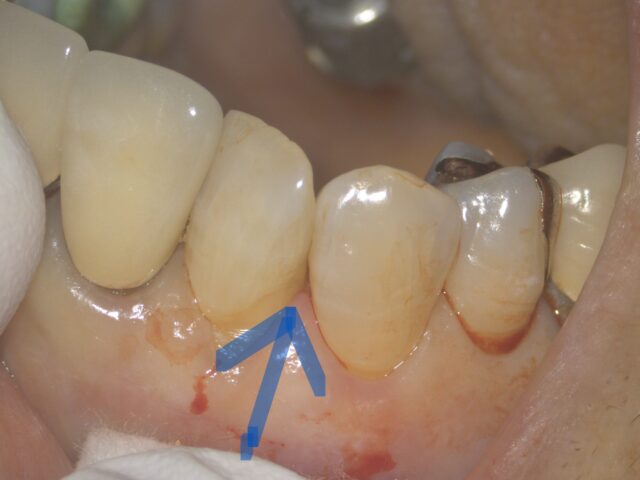

外側から見ても、虫歯は見えません。歯の並びが斜めになってます。

拡大して、裏から見ると歯の間に小さい虫歯が、黒く透けて見えてます。

このような部位の虫歯は、隣の歯の影に隠れてしまい、注意深く見ないと、見落とします。

セパレーターで歯の間を広げます。

歯間を広げる際にも、なるべく歯茎を傷つけないように、必要最小限にする必要があります。

しっかり虫歯を確認することが出来、

虫歯が見えてきました。